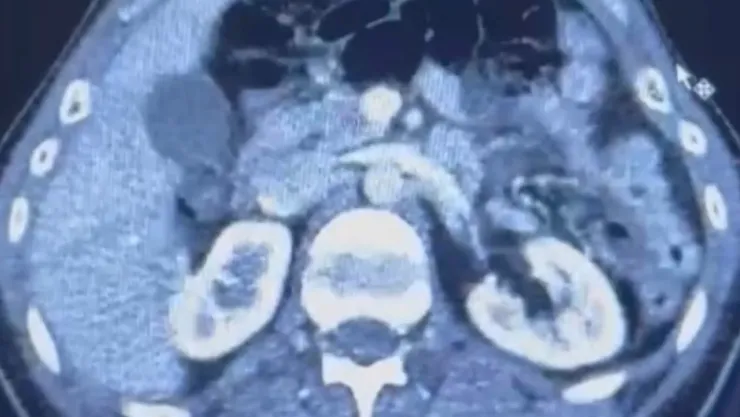

İran'dan Türkiye'ye uyuşturucu madde getirdiği tespit edilen 41 yaşındaki S.C., 35 yaşındaki R.B.C. ve 28 yaşındaki G.M. yakalandı ve yapılan aramalarda S.C. ve R.B.C.'nin Şehir Hastanesi'nde yapılan iç beden muayenelerinde mide kısımlarında 50 adet kapsül şeklinde 554 gram uyuşturucu madde tespit edildi.